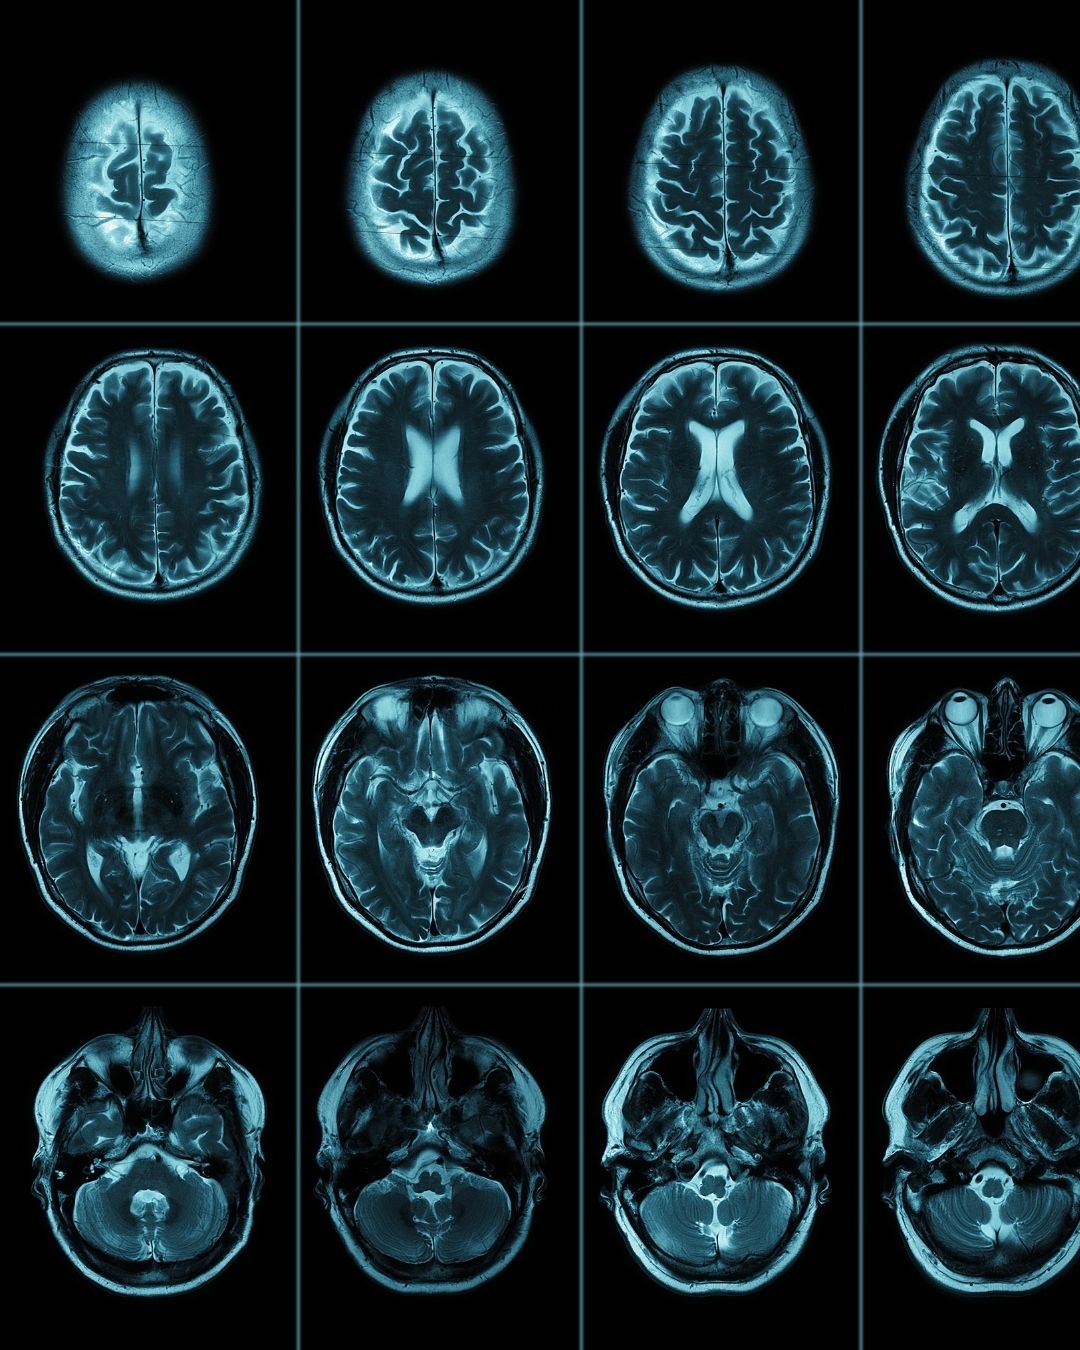

Kranial BT (Bilgisayarlı Tomografi), kafatası ve beyin yapılarının ayrıntılı olarak görüntülenmesini sağlayan bir radyolojik tetkiktir.

• X ışınları kullanılarak beynin ve kafatasının çok ince kesitli görüntüleri alınır.